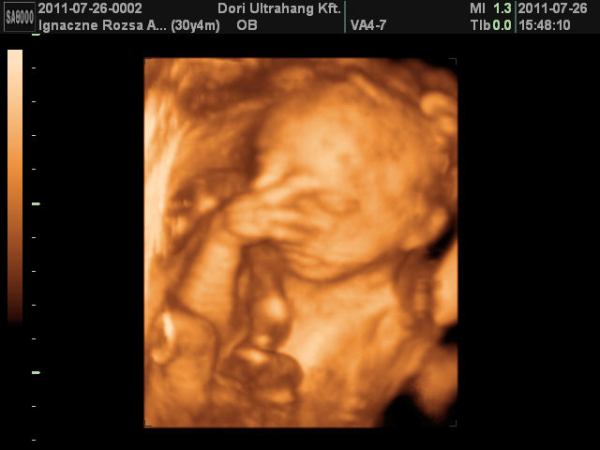

Mi jól vagyunk tegnap voltunk UH-n dobok malyd képet.

Milán sajna beteg volt ahogy már írtam, és szép pöttyeink is lettek.